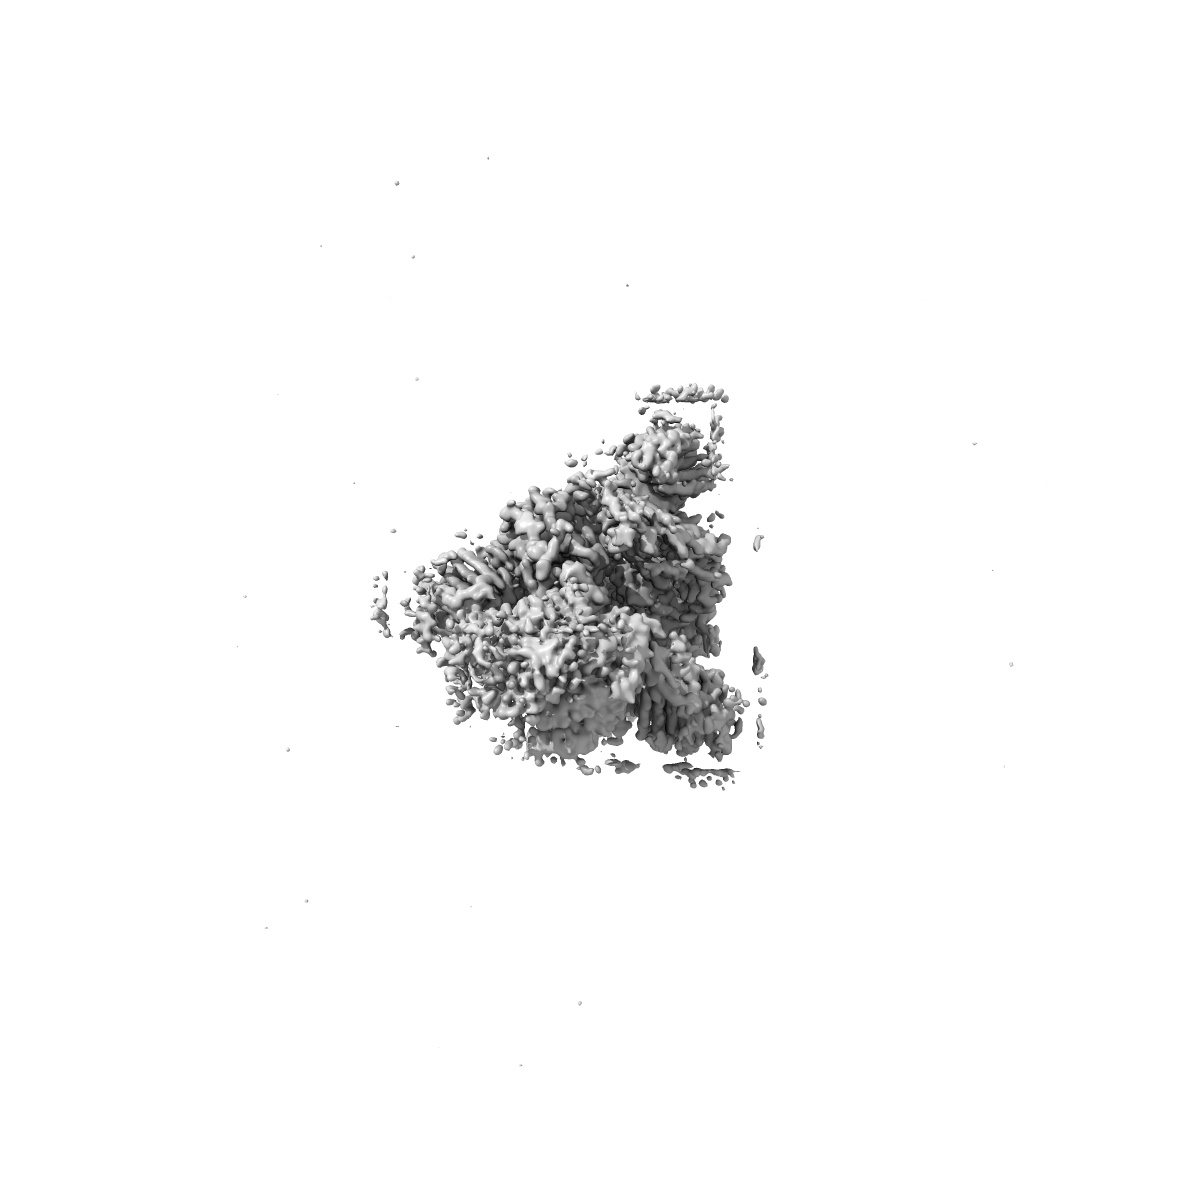

SARS-CoV-2 Omicron Variant SPIKE trimer complexed with ACE2

Single-particle2.77 Å

Sample: SARS-CoV-2 Omicron Variant SPIKE trimer complexed with ACE2

Fitted models: 7wpa

Structures of the Omicron spike trimer with ACE2 and an anti-Omicron antibody.

(2022) Science , 375 , 1048 - 1053